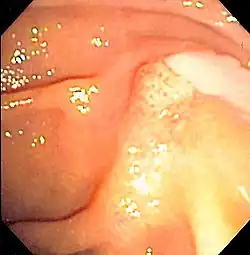

![]() | |

| Duodenoscopy image of pus extruding from the ampulla of Vater, indicative of cholangitis | |